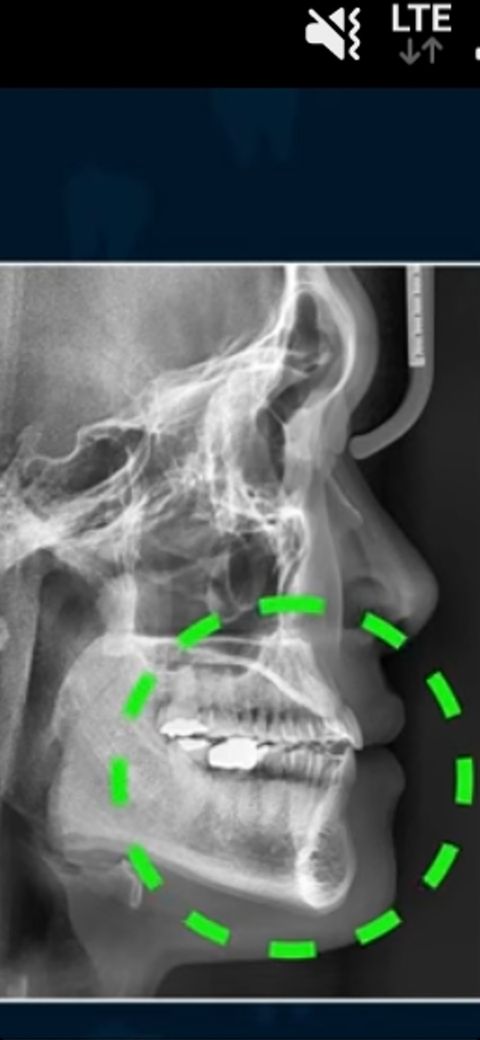

상악이 꺼진건가요 아니면 하악이 발달하고 상악이 정상인건가요

1.상악이 꺼진건가요 아니면 하악이 발달하고 상악이 꺼진건가요

2.코가 낮은 편인가요 높은편인가요

엑스레이만으로는 판단하기 어렵고 교정 분석을 해야 정확히 판단을 하실수 잇습니다. 저 사진을 찍으셧다면 교정 상담을 받으신거 같은데 결과를 알려주실꺼에요.